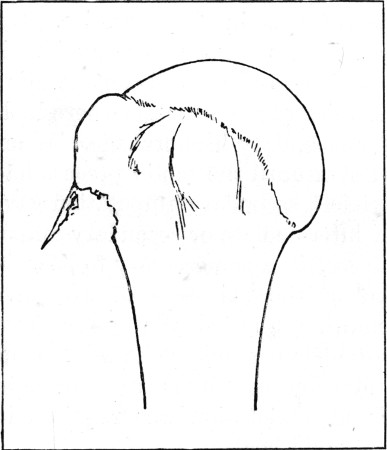

53a. Diagram of 'Butterfly' Type180

55a. Diagram of 'Butterfly' Type 200